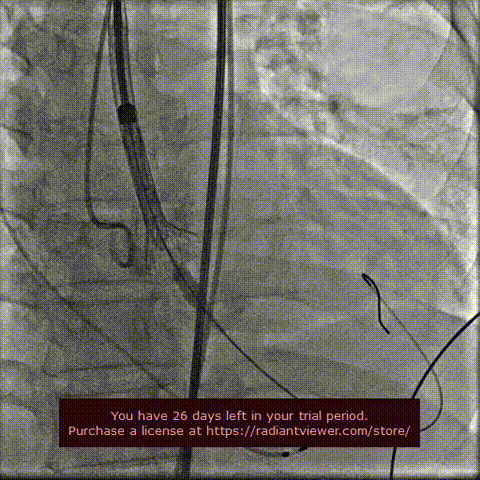

球囊扩张 :22mm球囊预扩,无漏,冠脉灌注良好,冠脉风险可控。

球囊预扩张